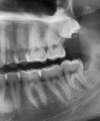

5/ Séance d'extraction de 2 dents de sagesse enclavées(en haut et en bas à gauche)... Pendant que le laboratoire de prothèse (Eric LOYAU) travaille sur les facettes selon nos consignes.